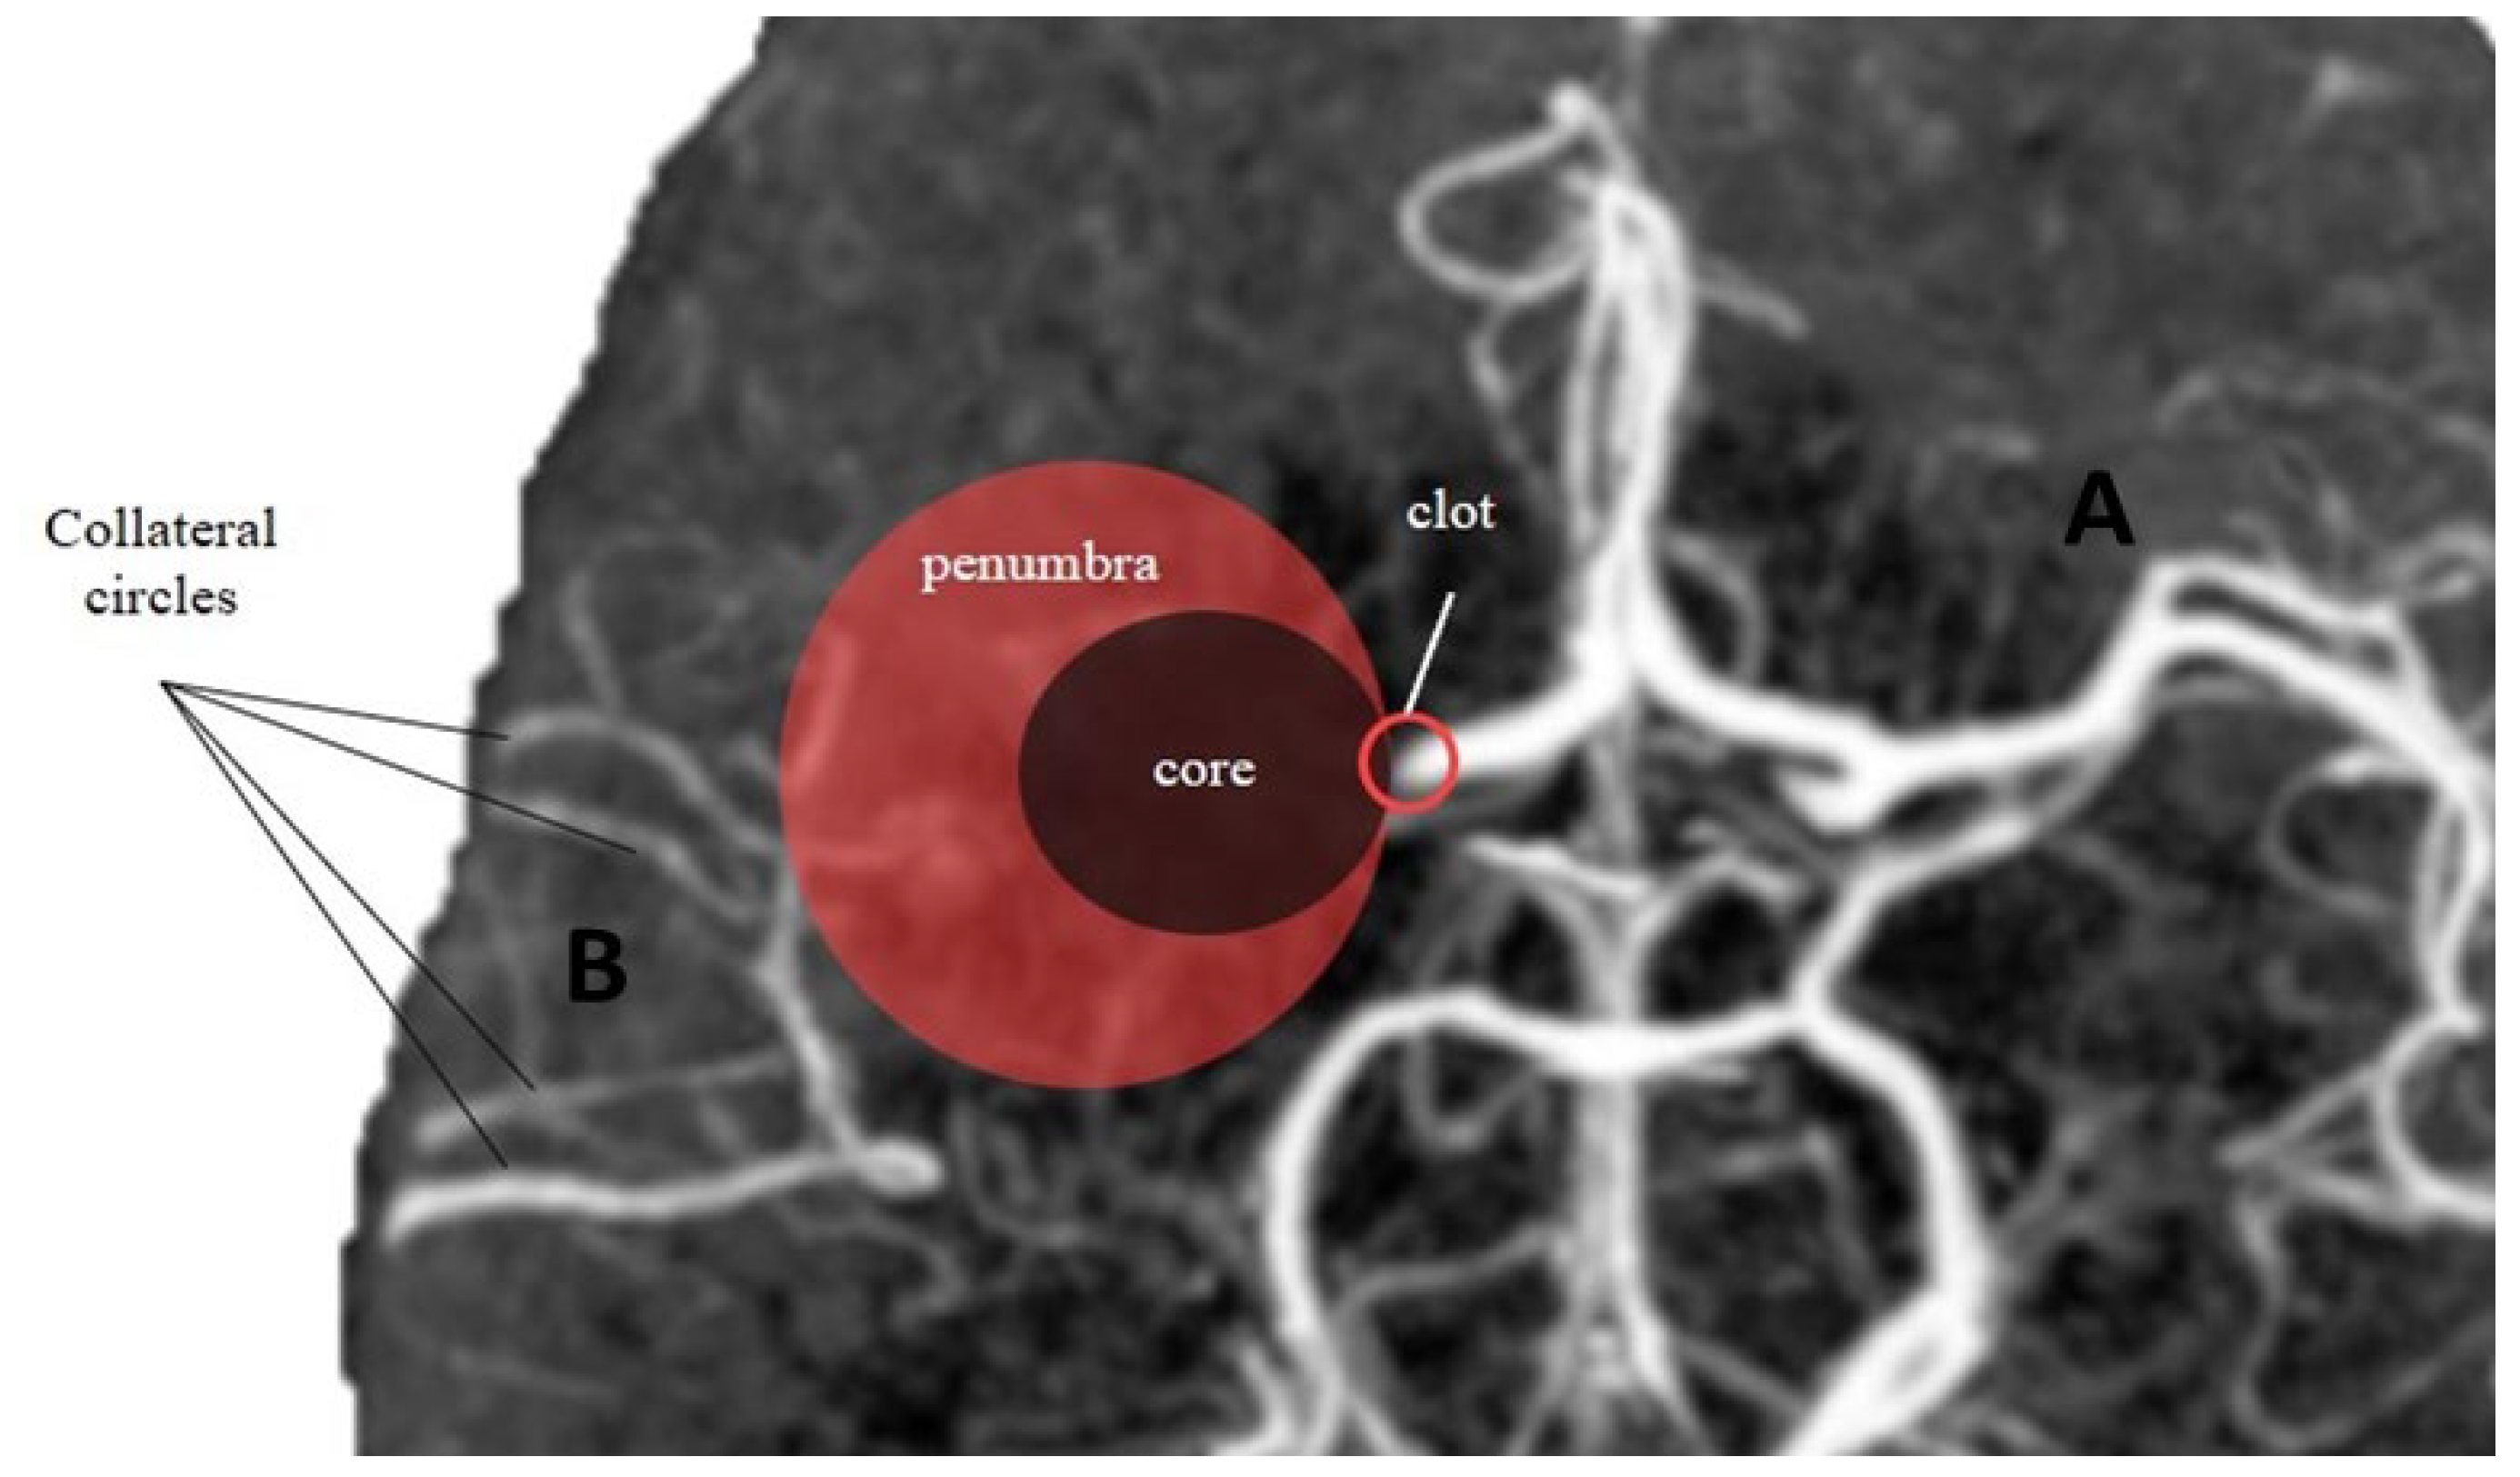

2.6. The Role of the “Core” and the “Penumbra”

3.2. Automatic Assessment